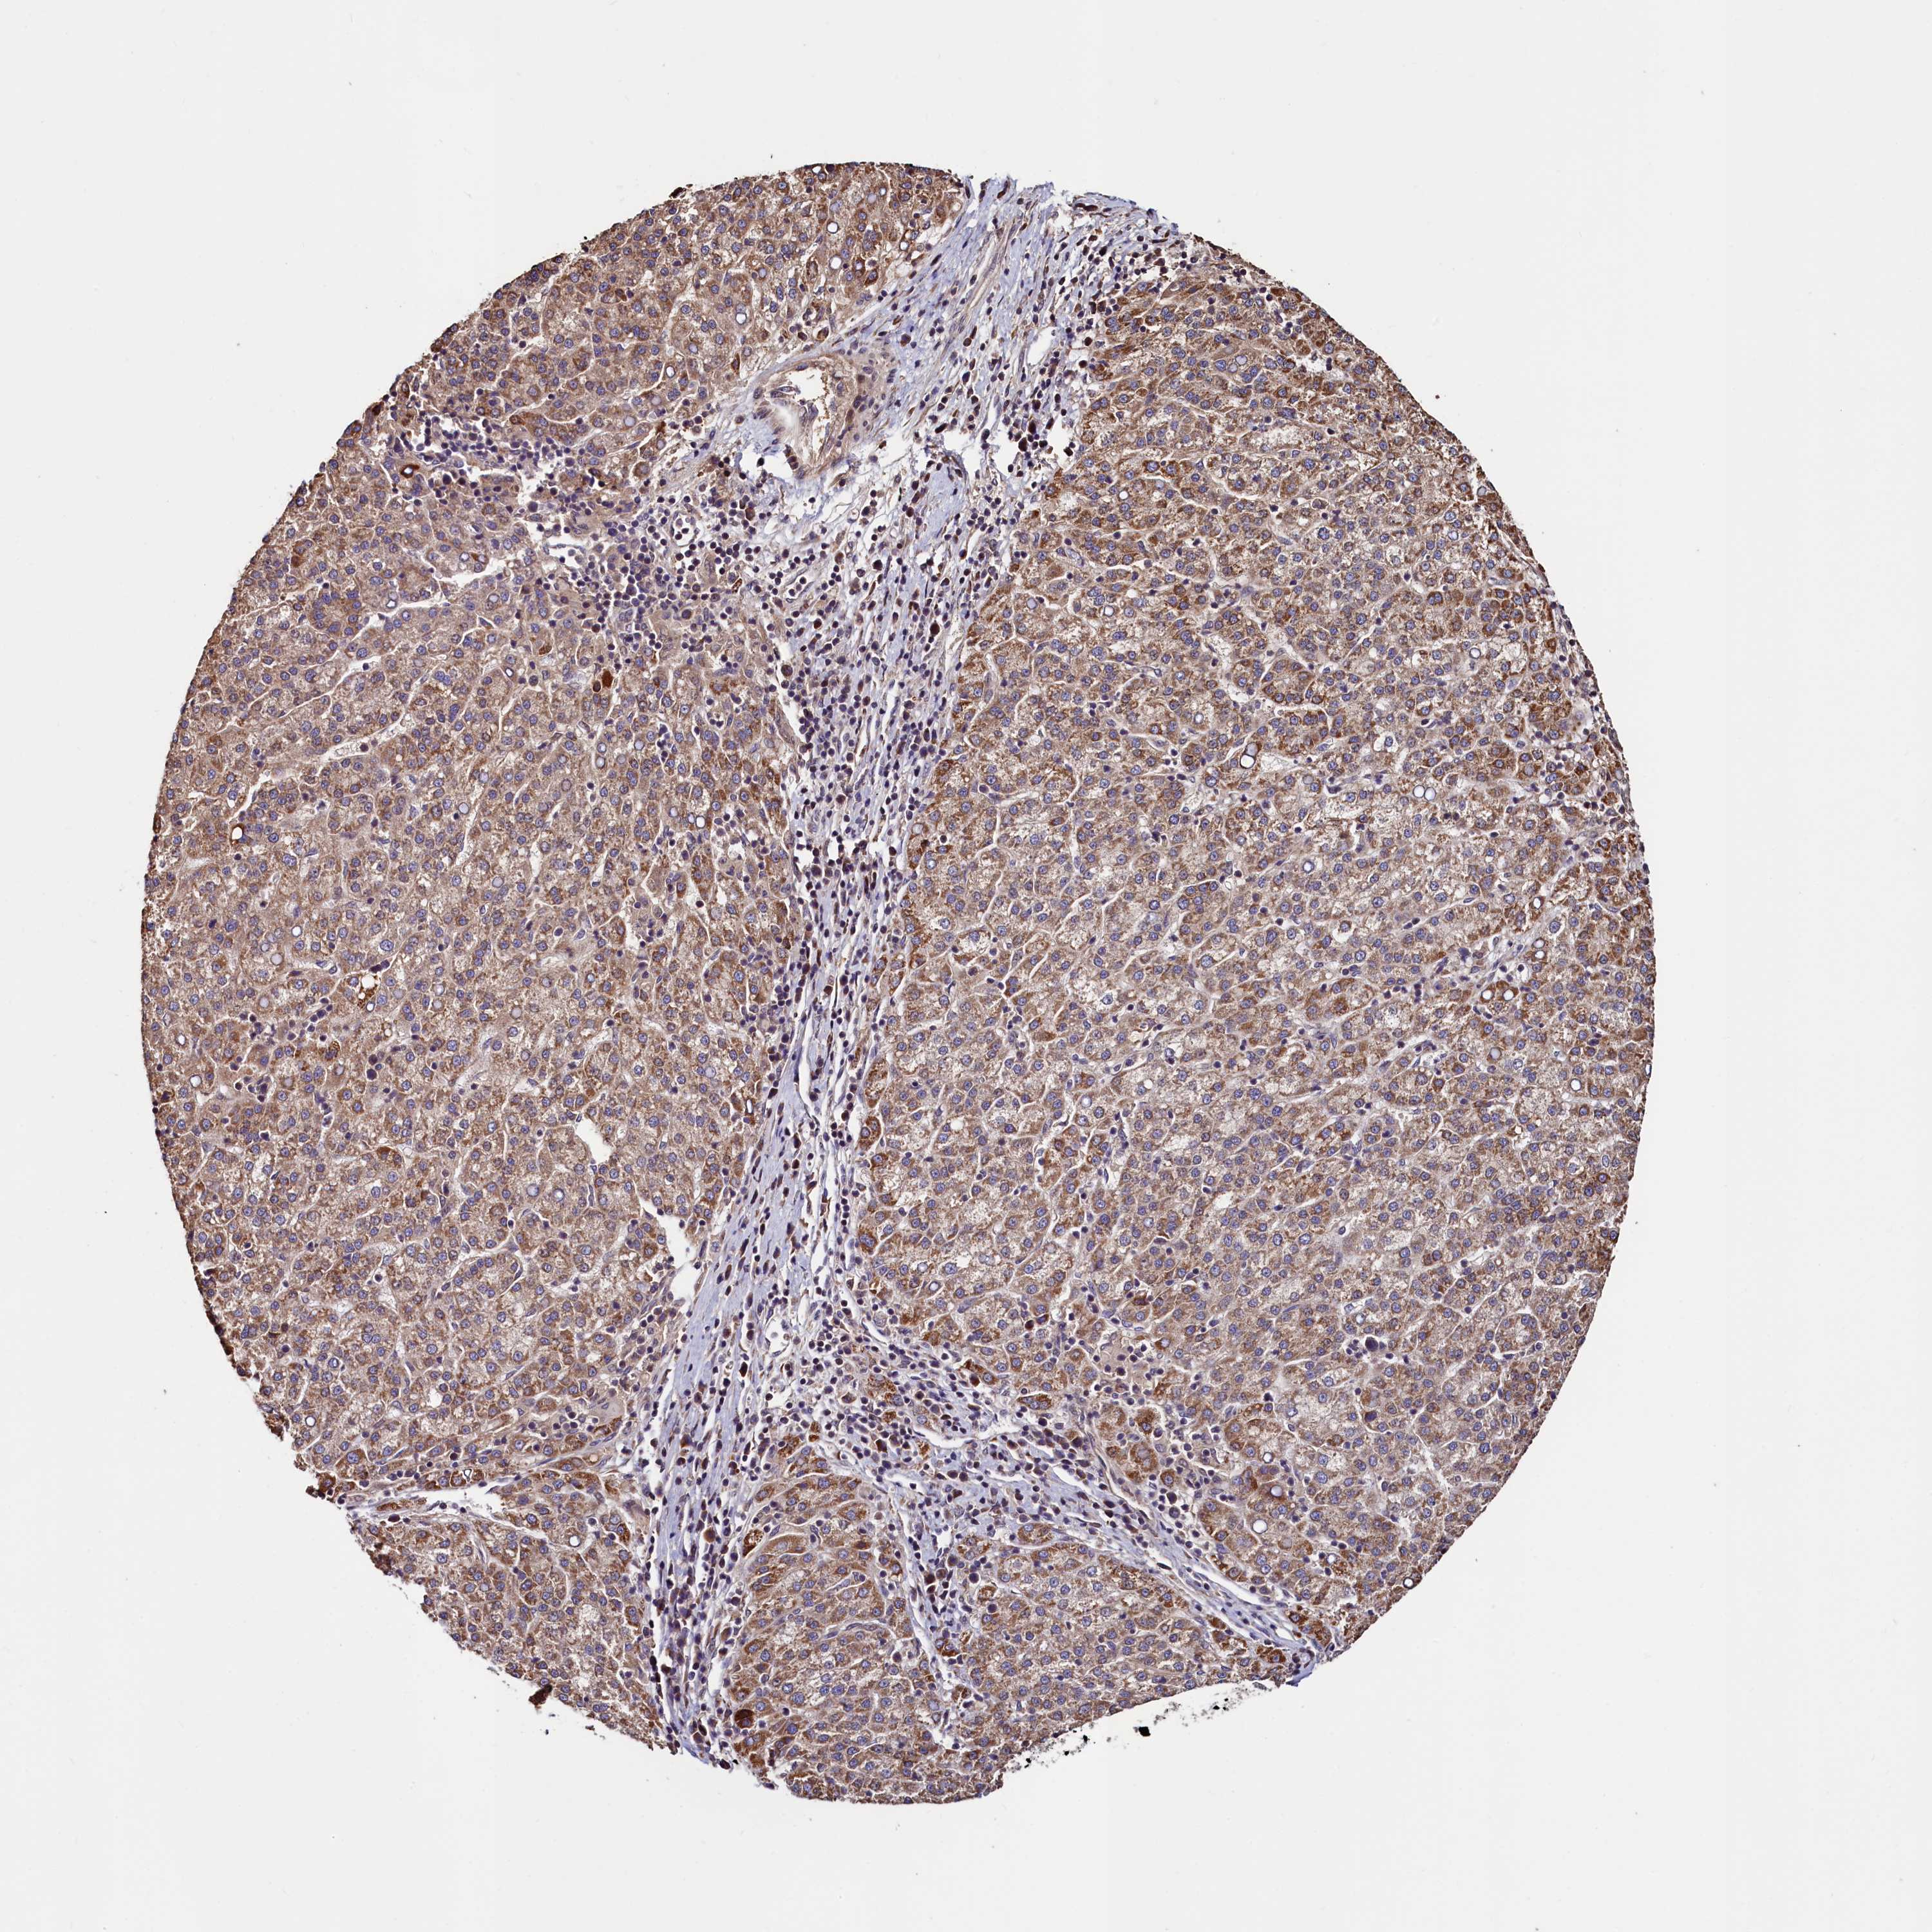

LIVER CANCER - Protein expressioni

A mouse-over function shows sample information and annotation data. Click on an image to view it in a full screen mode. Samples can be filtered based on level of antibody staining by selecting one or several of the following categories: high, medium, low and not detected. The assay and annotation is described here.

Note that samples used for immunohistochemistry by the Human Protein Atlas do not correspond to samples in the TCGA dataset.

Antibody stainingi

Antibody staining in the annotated cell types in the current human tissue is reported as not detected, low, medium, or high, based on conventional immunohistochemistry profiling in selected tissues. This score is based on the combination of the staining intensity and fraction of stained cells.

Each image is clickable and will lead to virtual microscopy that enables deeper exploration of all samples and also displays staining intensity scores, fraction scores and subcellular localization as well as patient and tissue information for each sample.

Antibody HPA040485

Antibody HPA041479

Staining

High

Medium

Low

Not detected

Intensity

Strong

Moderate

Weak

Negative

Quantity

>75%

75%-25%

<25%

None

Location

Nuclear

Cytoplasmic/membranous

Cytoplasmic/membranous,nuclear

Cholangiocarcinoma

Carcinoma, Hepatocellular, NOS